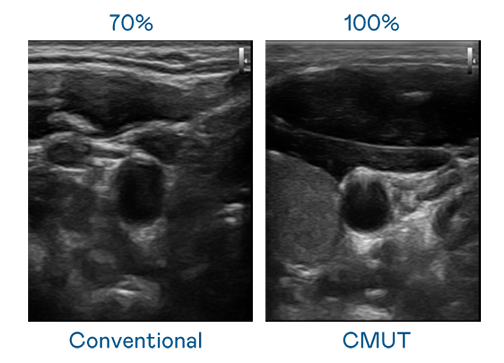

CMUT 技術是一種用電容式微機電元件來產生超音波訊號的技術。與傳統 PZT 壓電式技術相比,CMUT 頻寬增加 30%,更寬頻的超音波訊號讓影像解析度大幅提升,是實現高影像品質醫療超音波掃描、促進精準醫療發展的關鍵技術。

超音波影像的解析度高低,首先取決於探頭能發出的訊號頻寬。后宫露营第一季免费观看樱花动漫在线看 CMUT 可提供高清晰的超音波訊號,提供高頻寬、高靈敏度、影像紋理細節更高的超音波影像,協助醫護人員縮短影像判讀時間及利用精準的醫療影像進行診斷。